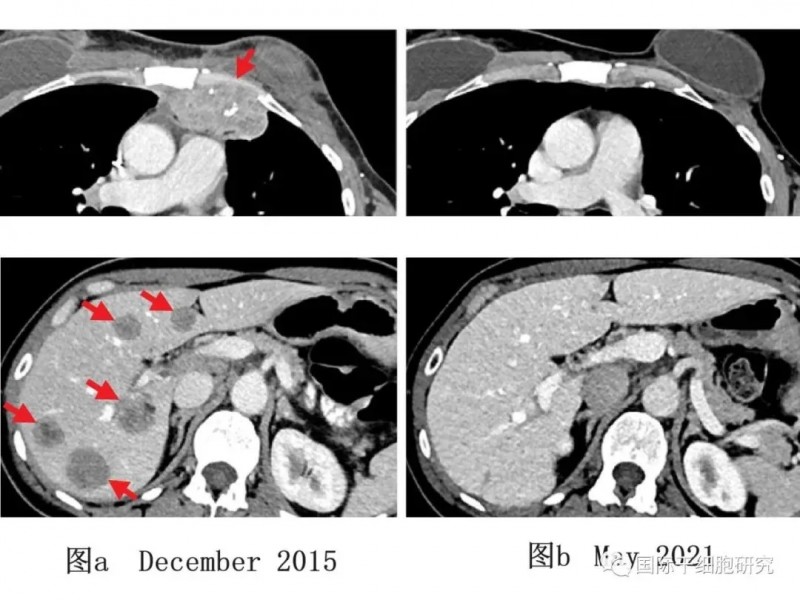

下图展示了一例乳腺癌患者TILs治疗前后影像学变化:下图a(2015年12月,治疗前)显示,患者胸壁(上,左)与肝脏(下,左)均存在转移性病变;下图b(2021年5月,经TILs免疫治疗后)显示,患者肿瘤完全消退,且随访5年未出现新发癌症。